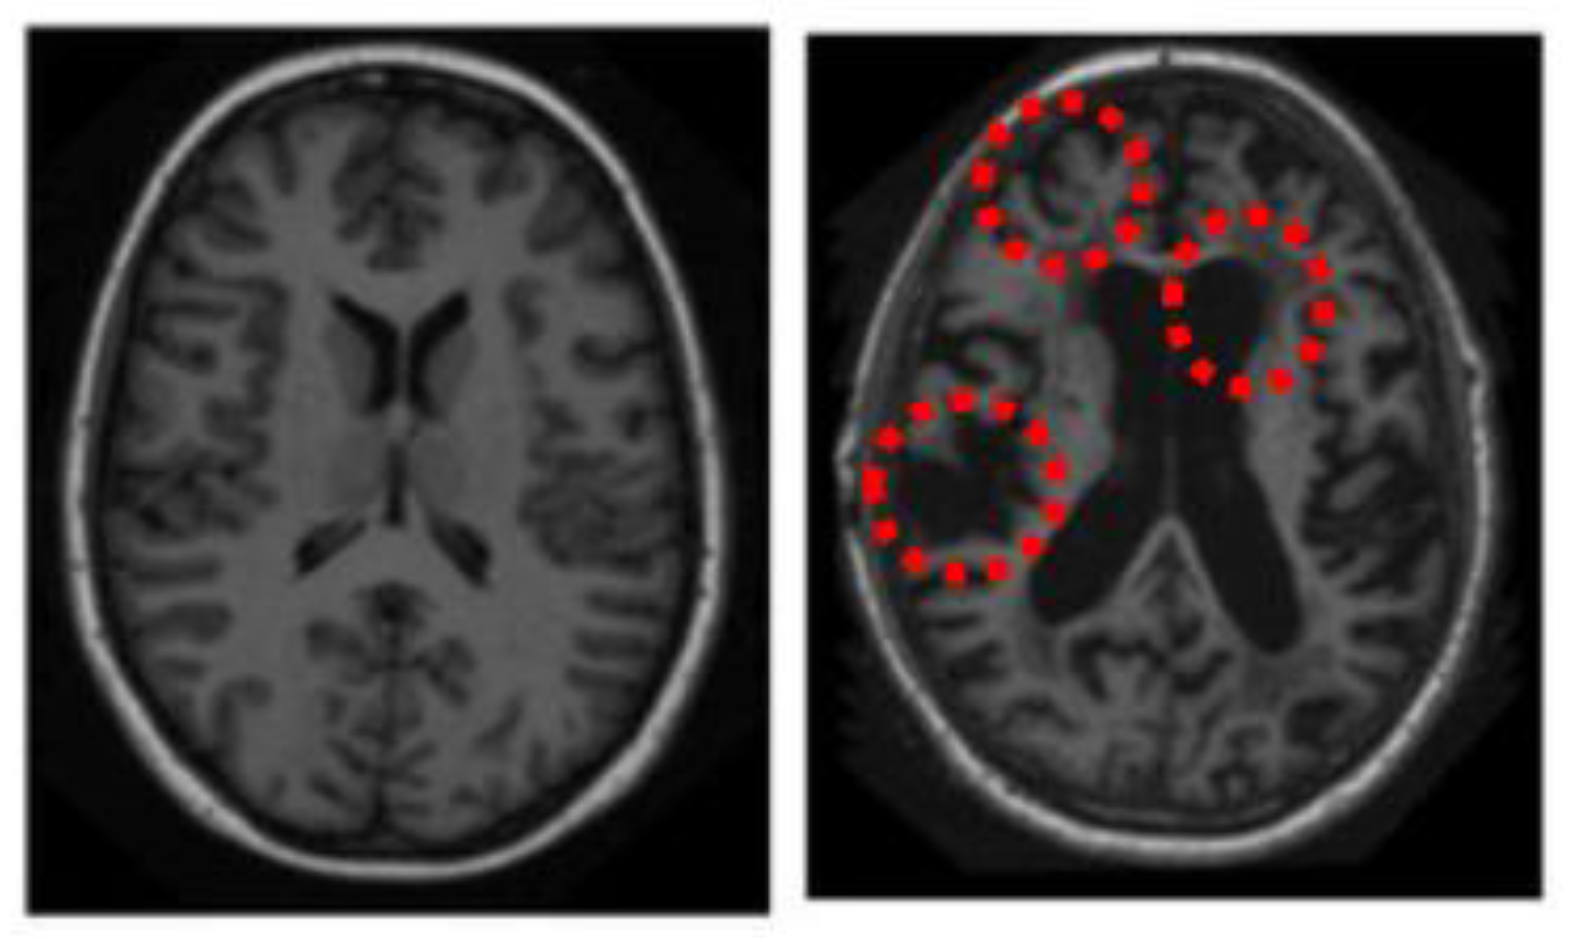

2.3.1. Top-Down Saliency Maps (

2.3.2. Bottom-Up Saliency Maps (

2.3.3. Final Saliency Map